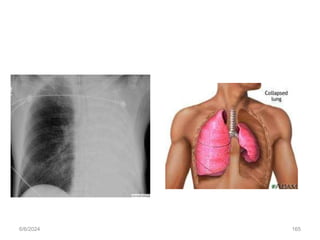

Atelectasis

• Atelectasis refers to closure or collapse of alveoli and often is described

in relation to x-ray findings and clinical signs and symptoms.

• may be acute or chronic

• May be micro atelectasis or macro atelectasis

• Causes

• Postoperative

• obstruction of airflow with mucus

• chronic airway obstruction by cancer

• Compression of lung tissue from effusion or a tumor

6/6/2024 165